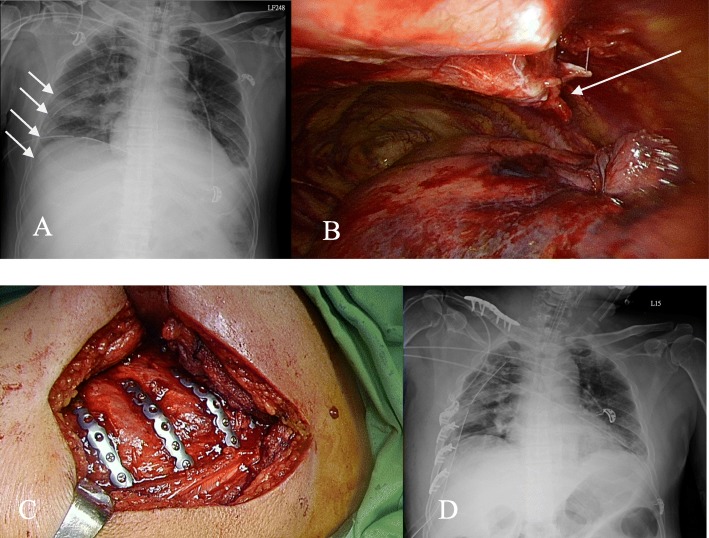

Fig. 1.

a Right side 5th to 8th rib bicortical fractures (white arrow) along with lung contusions. b VATS evacuation of hemothorax combined with localization of fractured rib (white arrow). c Fixation of fractured ribs using titanium plates with locking screws on the outer surface of ribs. d Chest X-ray after the operation

All surgical procedures were performed in operating rooms, and patients were under general anesthesia. As per our other studies [14, 15], in the VATS-only group, VATS was applied for the evacuation of residual blood clots and the resection of pulmonary lacerations under endoscopic visions. In patients who received rib fixation, VATS was also first used to treat the pleural and lung parenchyma lesions. The surgical wound incisions were then designed according to the fracture sites of the ribs that were localized using VATS (Fig. 1b). The fractured sites were approached using the chest wall muscle-sparing method [16–18]. Titanium plates with locking screws (MATRIXRIB™, products of DePuy Synthes, companies of Johnson & Johnson) that were specifically designed for fractured ribs were selected and applied at the outer surfaces of the ribs (Fig. 1c). One dose of first-generation cephalosporins as prophylactic antibiotics was administered before the operations.

After the operations, all patients underwent chest tube drainage. The chest tubes were connected to a low-pressure suction device (− 15 cm, H2O) to reduce residual pleural effusions (Fig. 1d). Ventilators were still applied after operations. A weaning ventilator protocol was planned. When patients achieved optimal oxygen saturation, their endotracheal tubes were removed. Chest tubes were removed when the air leaks were absent, and fluid drainage was less than 100 mL per day. Routine follow-up chest X-rays and close observations for wounds were performed after operations. Residual pleural effusions after operations were managed with secondary VATS. For patients who required ventilator dependence for longer than 14 days, tracheostomies were performed.